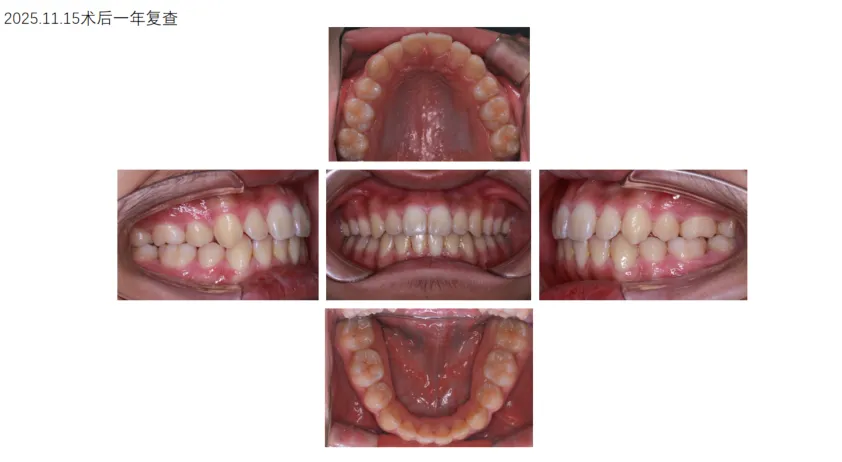

病例展示: